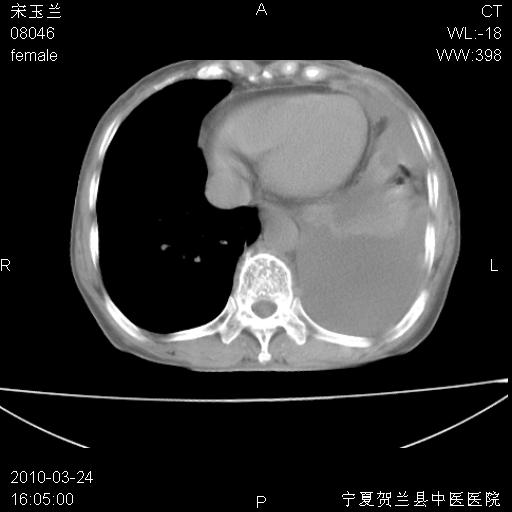

以下是引用随光逐影在2010-3-24 19:15:00的发言:[br]结合病史,考虑双肺及纵隔淋巴结多发转移、左侧胸膜转移并左侧大量胸水,左下肺膨胀不全。

以下是引用zxl51642在2010-3-24 18:49:00的发言:[br]结合乳腺癌术后病史,考虑双肺及纵隔淋巴结多发转移、左侧胸膜转移并左侧大量胸水、左下肺膨胀不全。